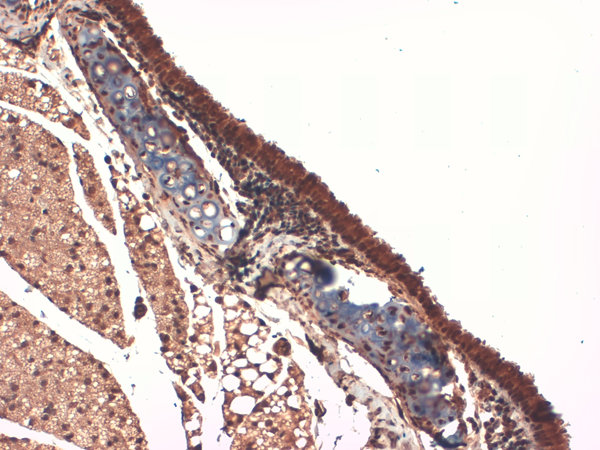

IHC (Immunohistochemisry)

(Immunohistochemistry analysis using Mouse Anti-Sodium Iodide Symporter Monoclonal Antibody, Clone 14F. Tissue: Trachea. Species: Mouse. Fixation: 10% Formalin Solution for 12-24 hours at RT. Primary Antibody: Mouse Anti-Sodium Iodide Symporter Monoclonal Antibody at 1:1000 for 1 hour at RT. Secondary Antibody: HRP/DAB Detection System: Biotinylated Goat Anti-Mouse, Streptavidin Peroxidase, DAB Chromogen (brown) for 30 minutes at RT. Counterstain: Mayer Hematoxylin (purple/blue) nuclear stain at 250-500 ul for 5 minutes at RT.)